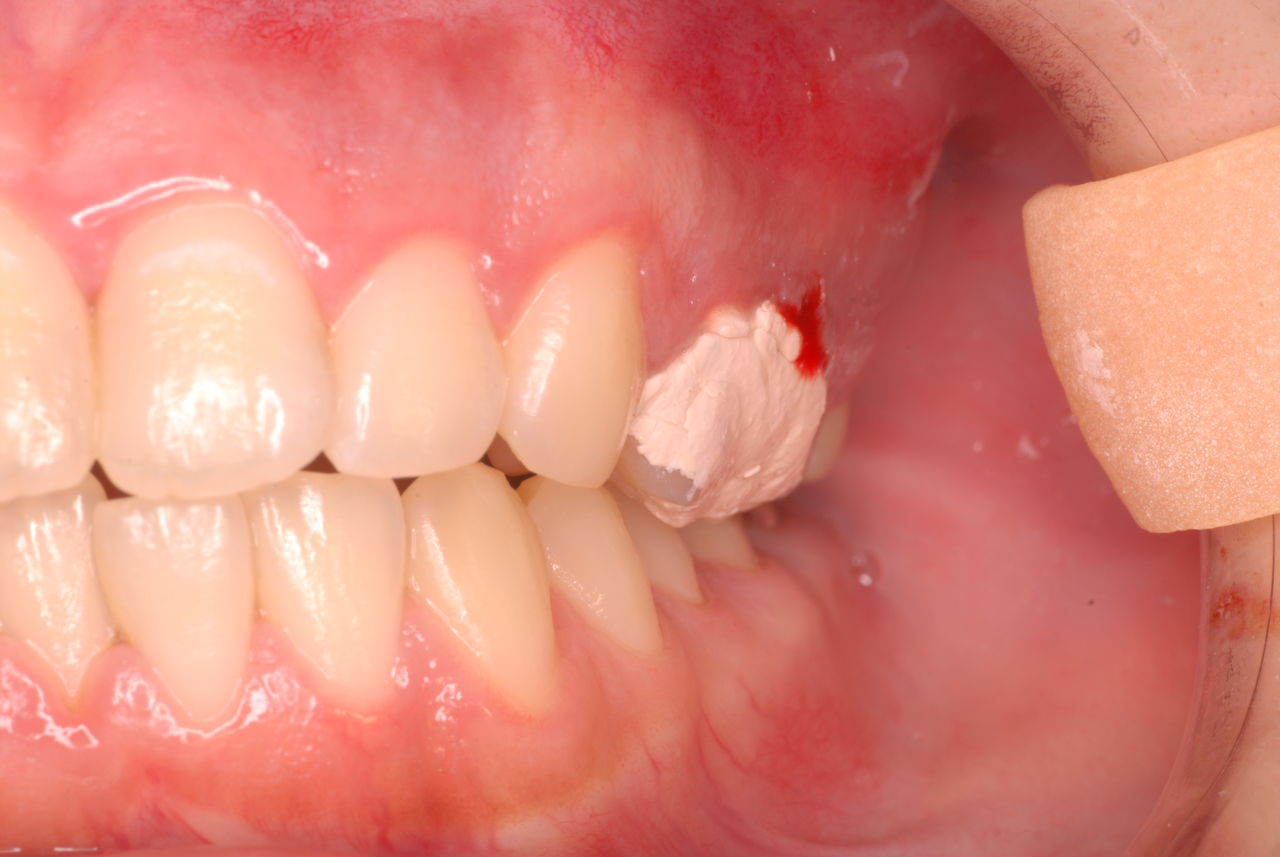

本当に患者さんのことを考えると憂鬱になります。歯周病が悪化すると殆ど回復は無理だからです。

抜いてインプラントにすれば収入は増えるでしょうし入れ歯にしても幾らかの費用はいただけるでしょう。

でもこれが医師?の考える事なのかと思えます。

制度を変えて、歯周病を治すことに対する評価を上げてもらうしか根本的解決はないのではと思った次第です。